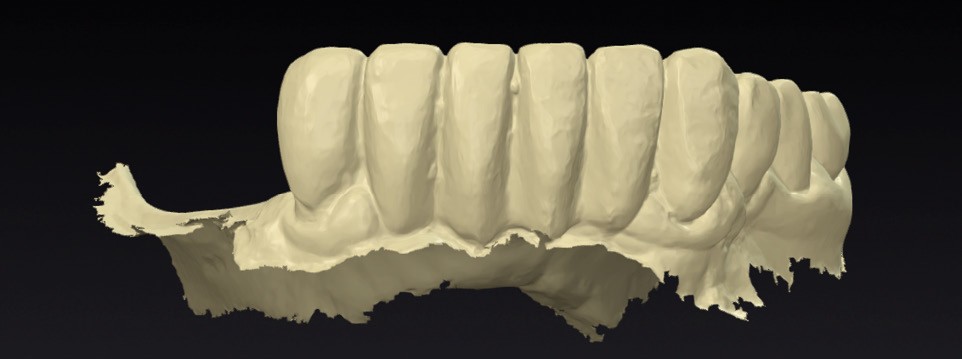

- les empreintes (fig. 3) transmises au laboratoire pour la réalisation d’un wax-up digital (fig. 4) préfigurant la position idéale des dents prothétiques. Ce modèle prothétique virtuel permet de déterminer la position, l’axe et la profondeur idéale des implants en fonction du couloir osseux, des tissus mous et du positionnement souhaité des puits de vissage.